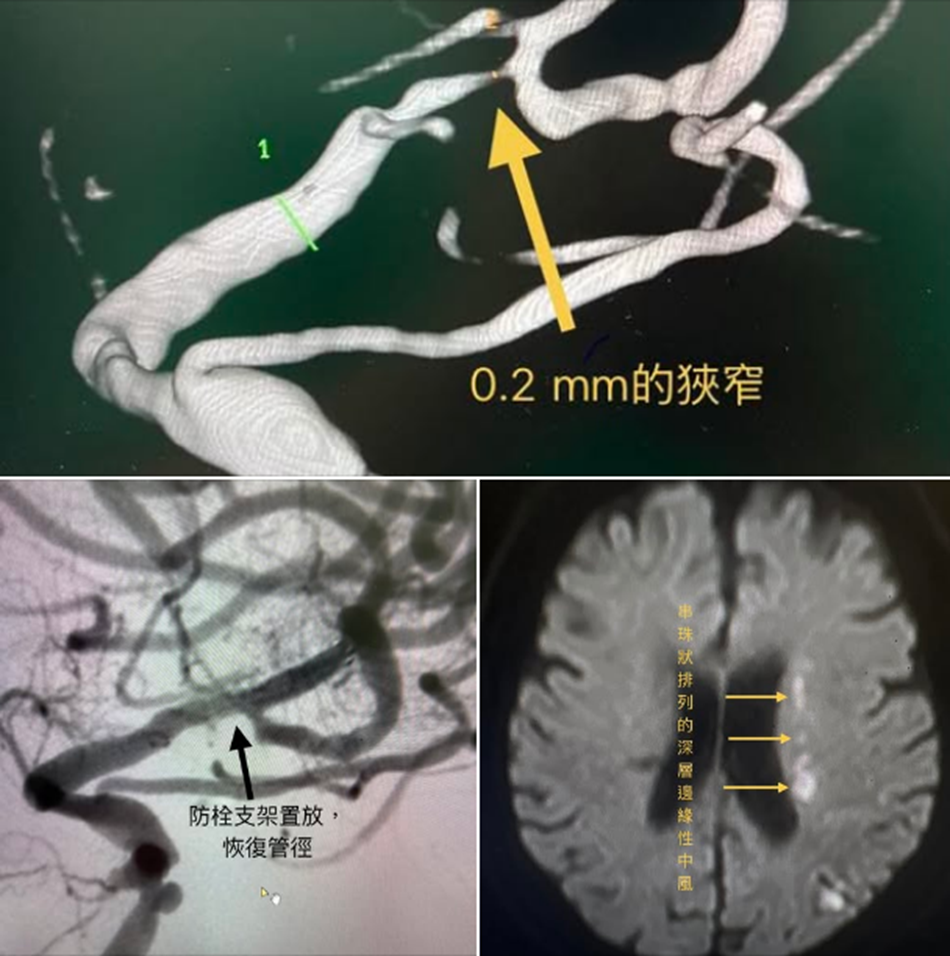

豐原七十歲女病人發生單側無力,本來有好些,但又突然變壞!來回多次。MRI檢查發現典型的側腦室旁串珠排列白點;MRA及血管攝影發現左邊腦血管91% 狹窄,管徑只剩下0.2 mm。這解釋了她的症狀隨著血壓而波動。這種不穩定,其實是一個警訊,表示血管的循環已到崩潰的臨界點,一旦血流再不足就會血管完全堵塞。幫她申請了健保防栓塗層顱內支架。置放完後,症狀變得穩定,沒有再反覆。目前復健已經到可以用助行器走路。

所以不穩定有時更要小心,不是會變好,而是崩潰前的警訊!就好像日光燈的變壓器,當它不穩,造成日光燈一閃一閃,就是快壞了!